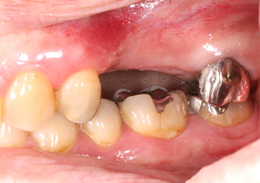

ショートインプラント使用し骨造成をしないグラフト術式

- 主訴

- 左上ブリッジの支台であった左上5を歯根破折でばっしとなり左上56の欠損となった

- 治療内容

- 抜歯から3ヶ月の治癒期間を経てCT撮影を行った結果、通常であれば上顎洞挙上手術の対象となるケースが多いが、ショートインプラントを用いることで大規模な骨造成お回避できることがわかった。2本ショートインプラント埋入

- 治療費用

- 900,000円(税別)

- 治療期間

- 5ヶ月